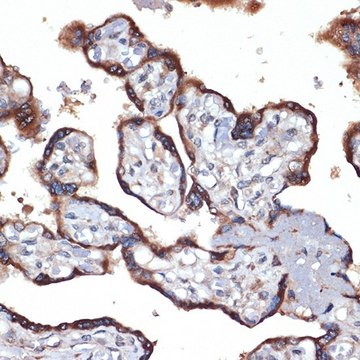

Anti-TMEFF2 antibody produced in rabbit

Anti-Hyperplastic polyposis protein 1, Anti-TR-2, Anti-Tomoregulin-2 precursor, Anti-Transmembrane protein with EGF-like and two follistatin-like domains